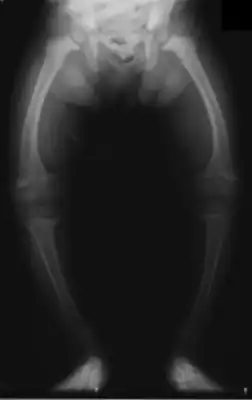

![]() Искривление нижних конечностей у 2-летнего ребёнка, страдающего рахитом *. | |